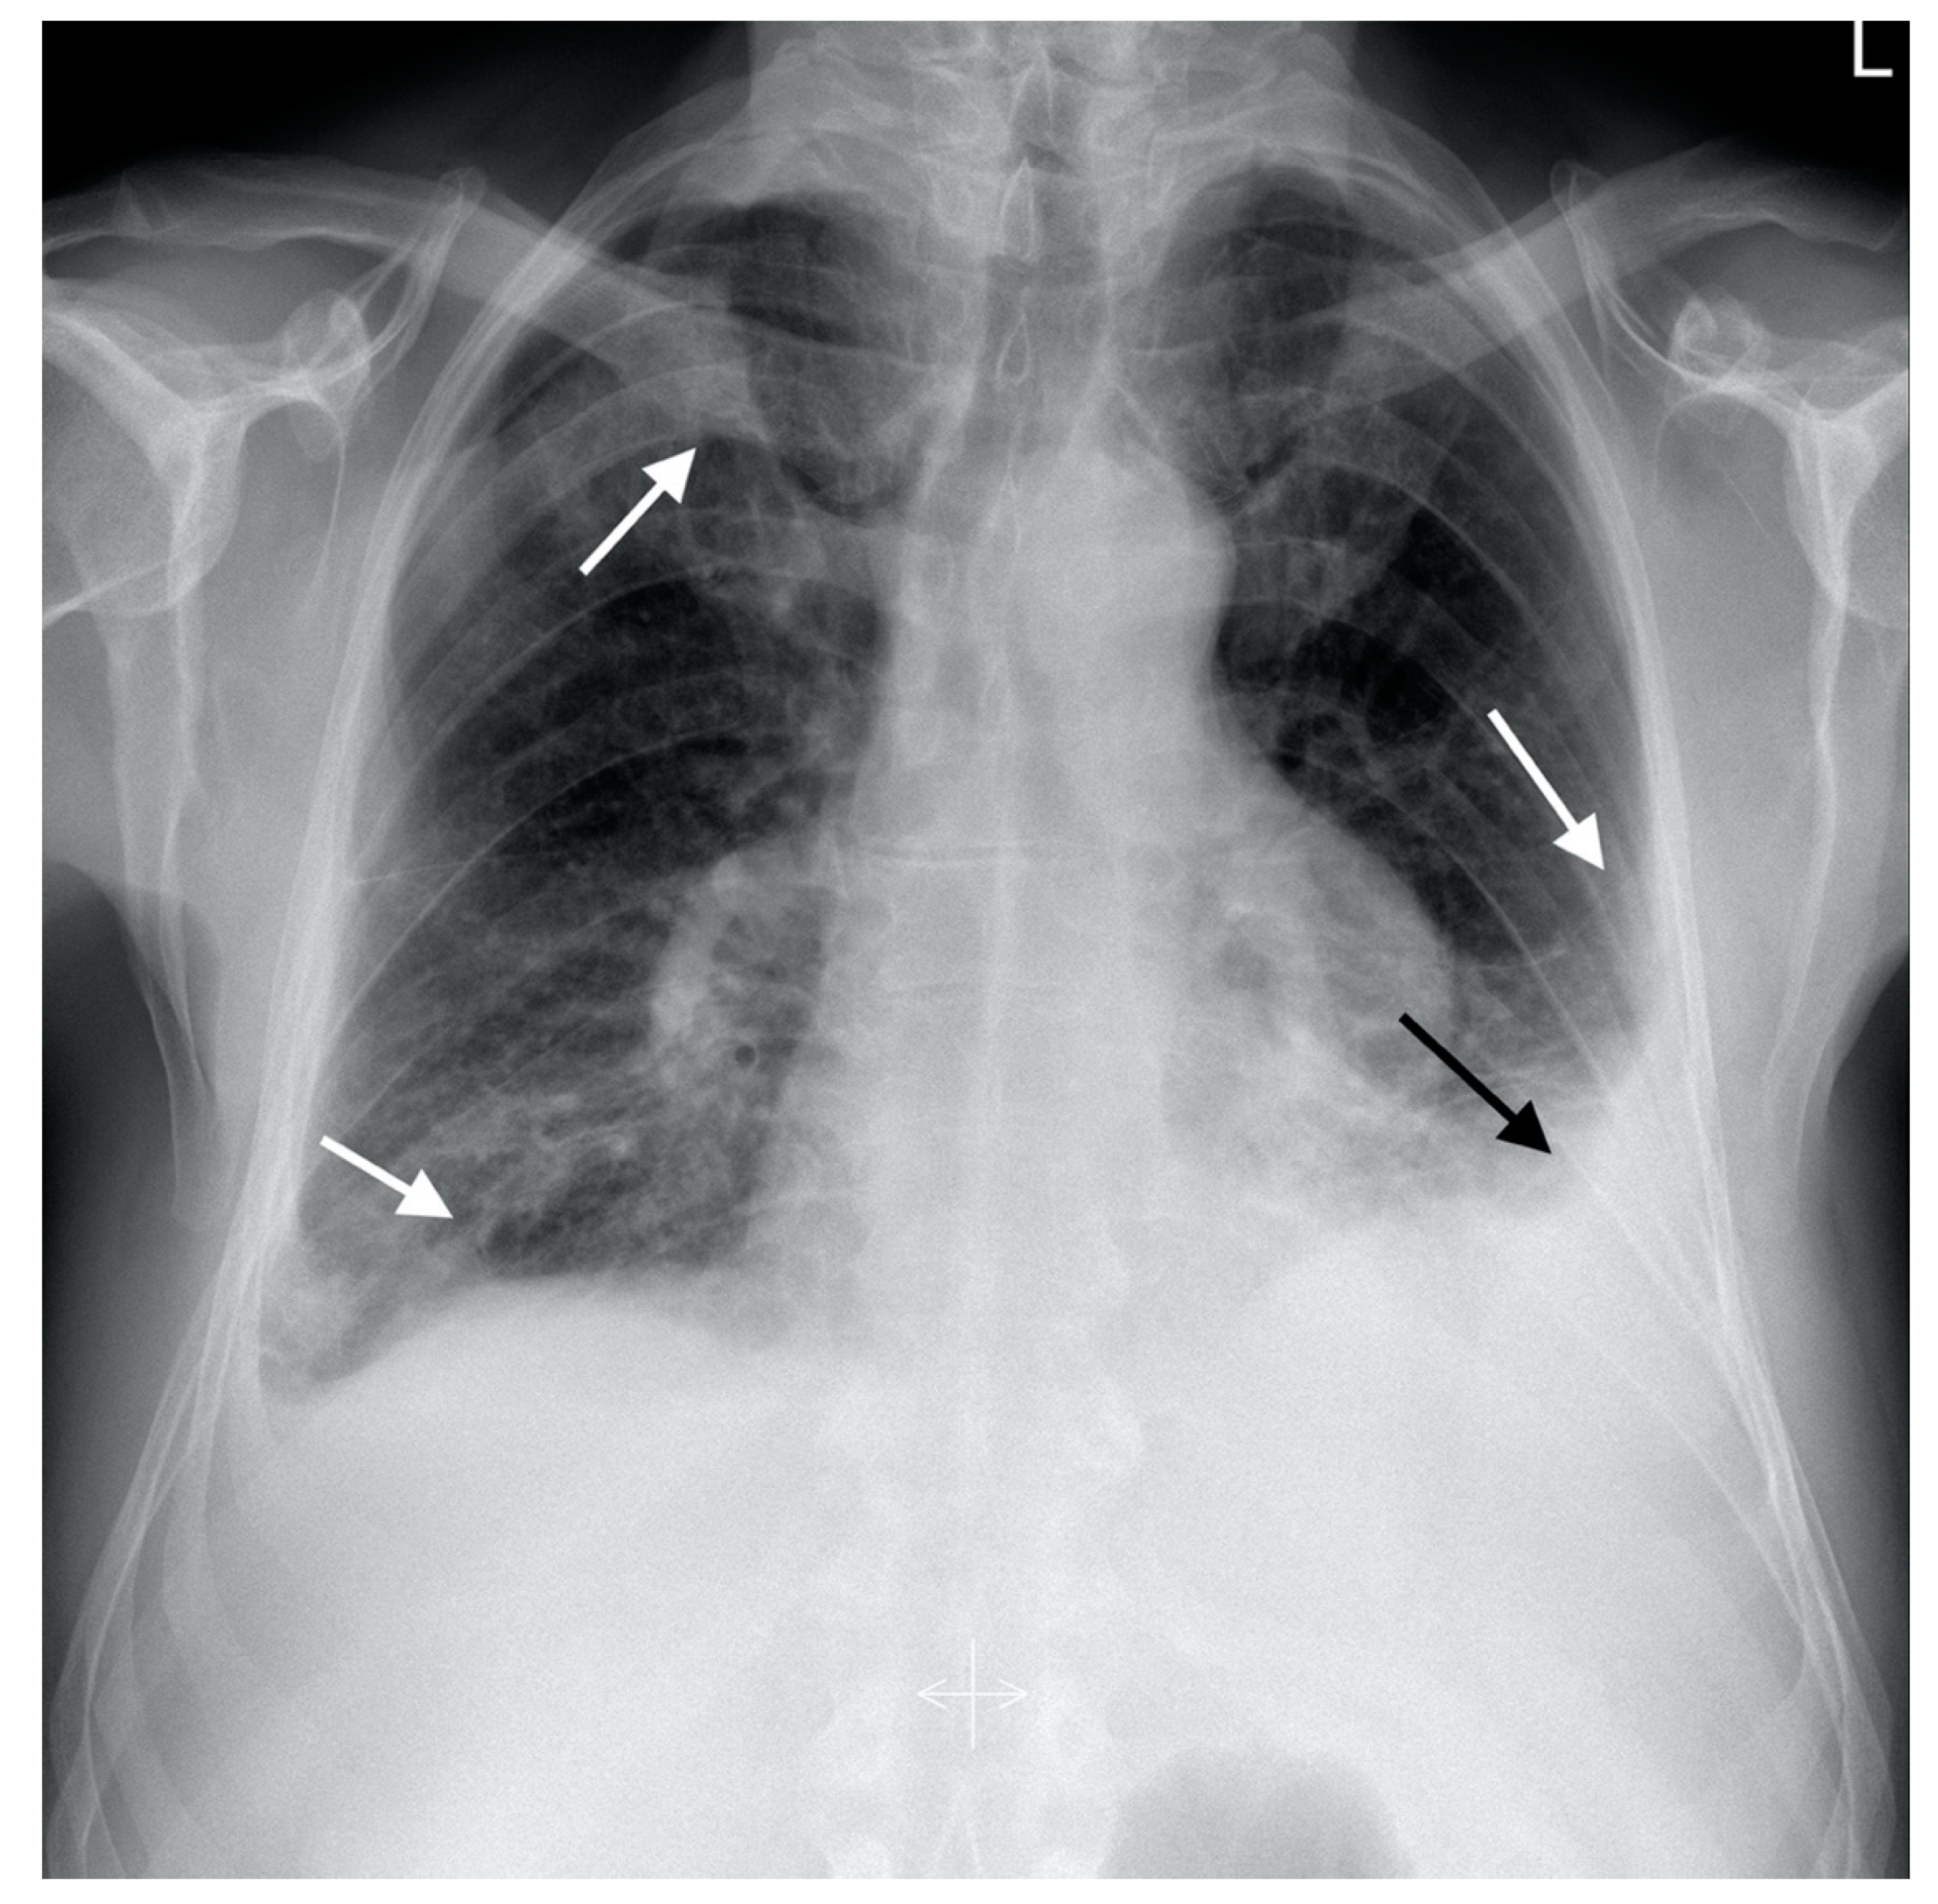

| Radiological picture | Pulmonary embolism, parenchymal infiltrates, bilateral pleural fluid | Regression of PA thrombi, pleural fluid and parenchymal consolidations | Complete resolution of PA thrombi, pleural fluid and lung consolidations | |